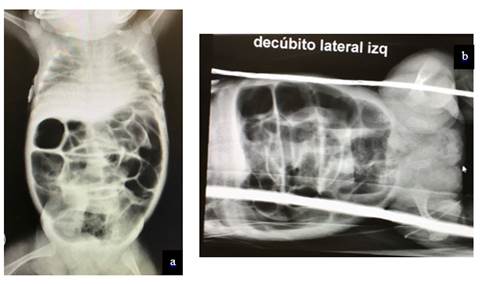

Se solicitó una radiografía de abdomen que evidenció una gran distensión de asas intestinales, sin niveles hidroaéreos. No se observó neumoperitoneo, ni imágenes de neumatosis intestinal (Figura 1a y b).

Figura 1 (a y b): Rx de abdomen de la paciente que muestran una gran distensión gaseosa de todo el intestino, sin presencia de niveles hidroaéreos o neumoperitoneo.

En cuanto a los estudios de imágenes, si bien la radiografía simple de abdomen puede tener cierta utilidad para plantear la sospecha clínica, cuando se encuentra distensión gastro duodenal -eventualmente con niveles hidroaéreos-, y ausencia de gases distales al duodeno comprometido en el pie del vólvulo, como se esboza en nuestro segundo paciente (no hay dilatación, pero si franca disminución de los gases distales), la misma es muy inespecífica y puede no aportar ningún elemento orientador, como ocurrió en nuestro primer paciente, que presentó una radiografía de abdomen con distensión gaseosa sin niveles hidroaéreos de todo el intestino, que incluso llegaba a simular un marco cólico normal, y en la que tampoco se apreció neumoperitoneo, a pesar de la perforación intestinal comprobada luego durante la cirugía.